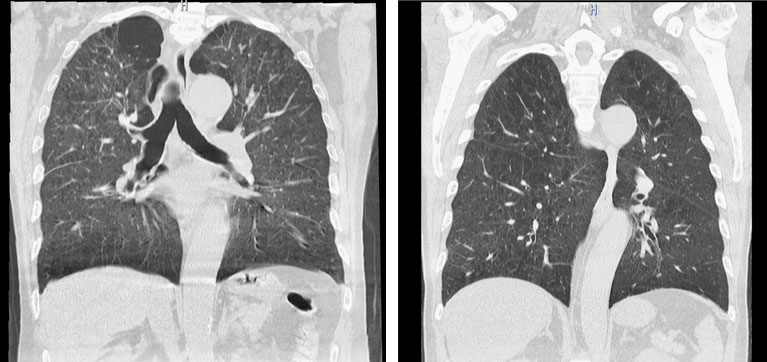

慢性閉塞性肺疾患(COPD)

慢性閉塞性肺疾患とは、従来、慢性気管支炎や肺気腫と呼ばれてきた病気の総称で、タバコの煙を主とする有害物質を長期に吸入することで生じる炎症性疾患です。症状は身体を動かした時に息切れを感じる労作時呼吸困難や慢性のせきやたんが特徴的です。一部の患者では、喘鳴や発作性呼吸困難など喘息の様な症状を合併する場合もあります。呼吸機能検査を行うことで今の肺の機能を正確に捉え、生活上の注意や治療の参考にします。